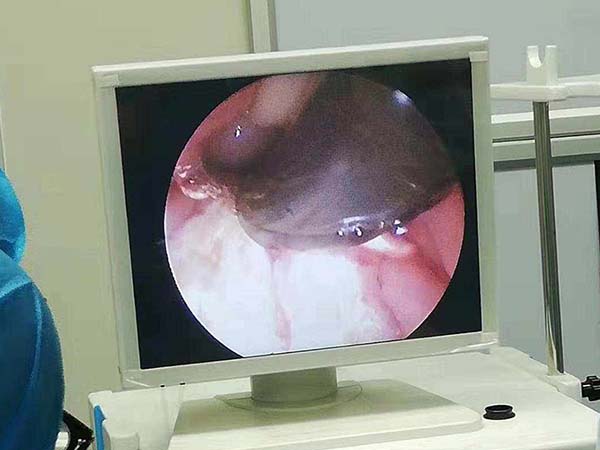

此外,腺樣體手術需要用等離子刀或者鼻用電動切割器切除肥大的腺樣體組織,手術後會產生創口,如果手術時腺樣體殘留、鼻咽部血管受損、或是止血不及時都會導致出血不止,影響患兒身體健康。

腺樣體肥大影響了呼吸,如睡眠打鼾、身體或智力發育遲緩、腺樣體面容等症狀出現時,通過手術切除腺樣體,可以及時改善進氣道的通暢,解決腺樣體形成的病理性改變。